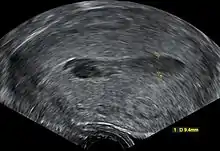

| Transvaginal ultrasonography of a hematometra after childbirth, seen as a hypoechoic (darker) area within the uterine cavity. The cervix is located to the left in the image, and the fundus is located to the right. | |

Although hematometra can often be diagnosed based purely on the patient's history of amenorrhea and cyclic abdominal pain, as well as a palpable pelvic mass on examination, the diagnosis can be confirmed by ultrasound, which will show blood pooled in the uterus and an enlargement of the uterine cavity.[4][5] A pyelogram or laparoscopy may assist in diagnosing any congenital disorder that is suspected to be the underlying cause of the hematometra.[2]